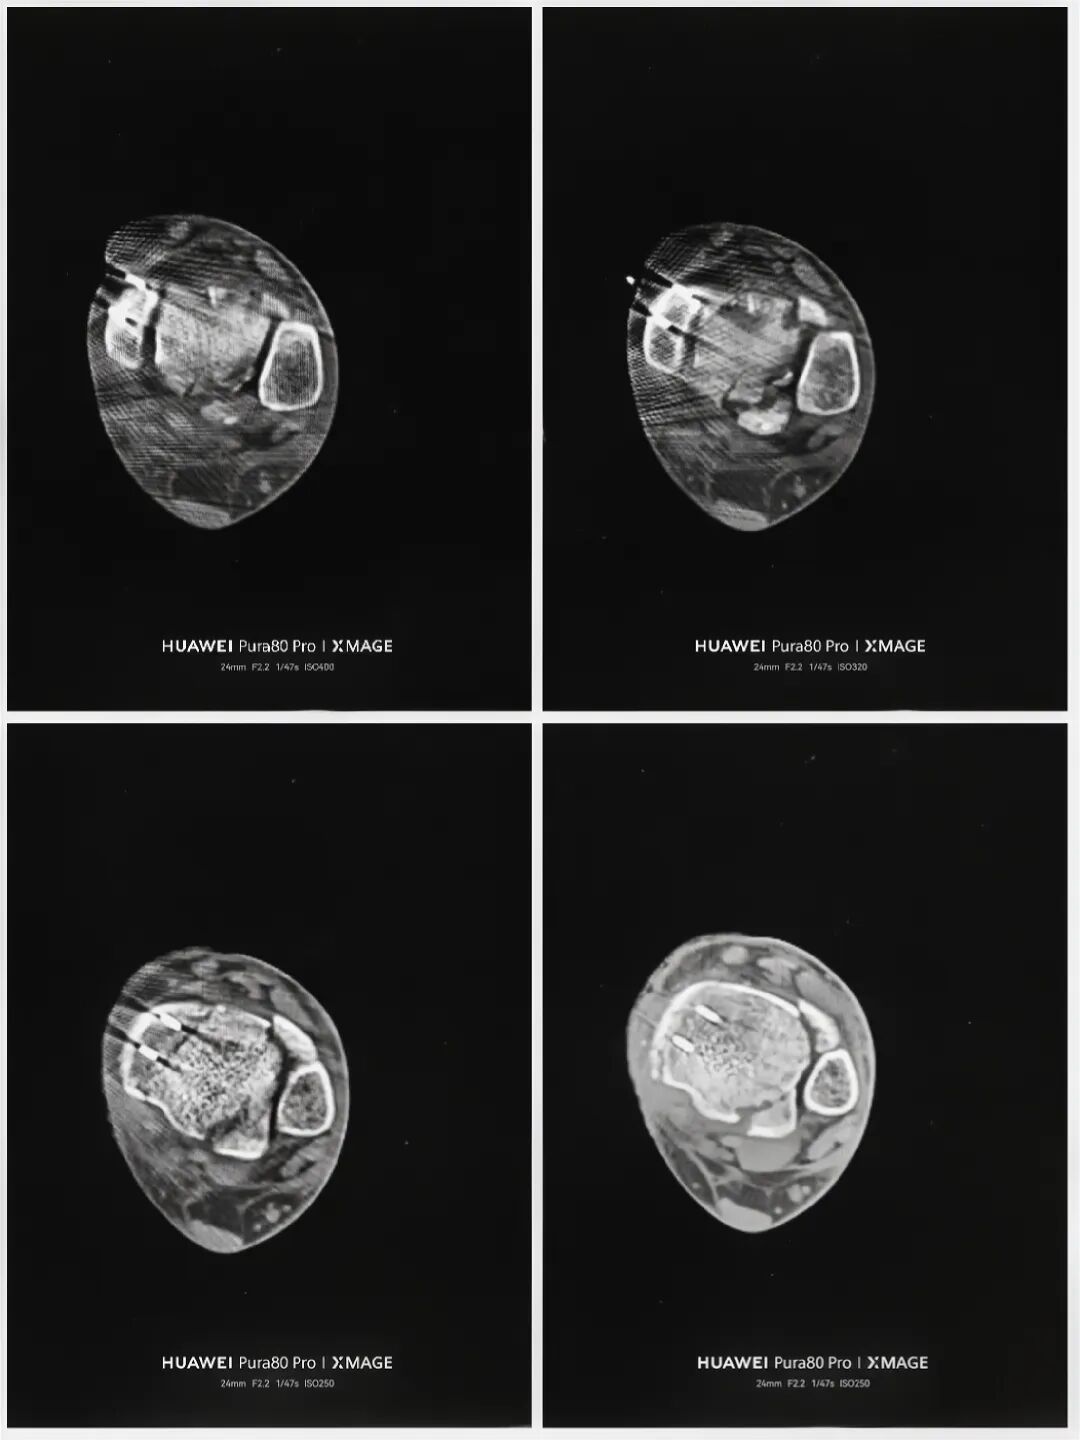

解剖复位

最后做下胫腓

两个位置螺钉固定

下胫腓关节复位

内踝间隙恢复